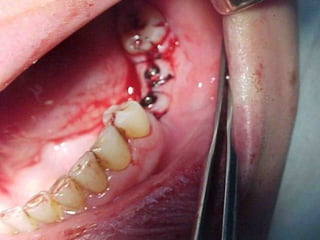

Plastia de maxilares para implantes dentales.

La conformación quirúrgica de un contorno alveolar adecuado es

determinante para la correcta aplicación y aceptación de los implantes

de titanio, aquí proponemos una técinica para lograr el espesor óseo

suficiente y la corrección estética del proceso, ya que antiguamente al

extraer un diente se acostumbraba presionar las tablas alveolares

“para cohibir la hemorragia”, con el colapso subsiguiente de la región.